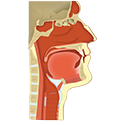

NEUROANATOMY